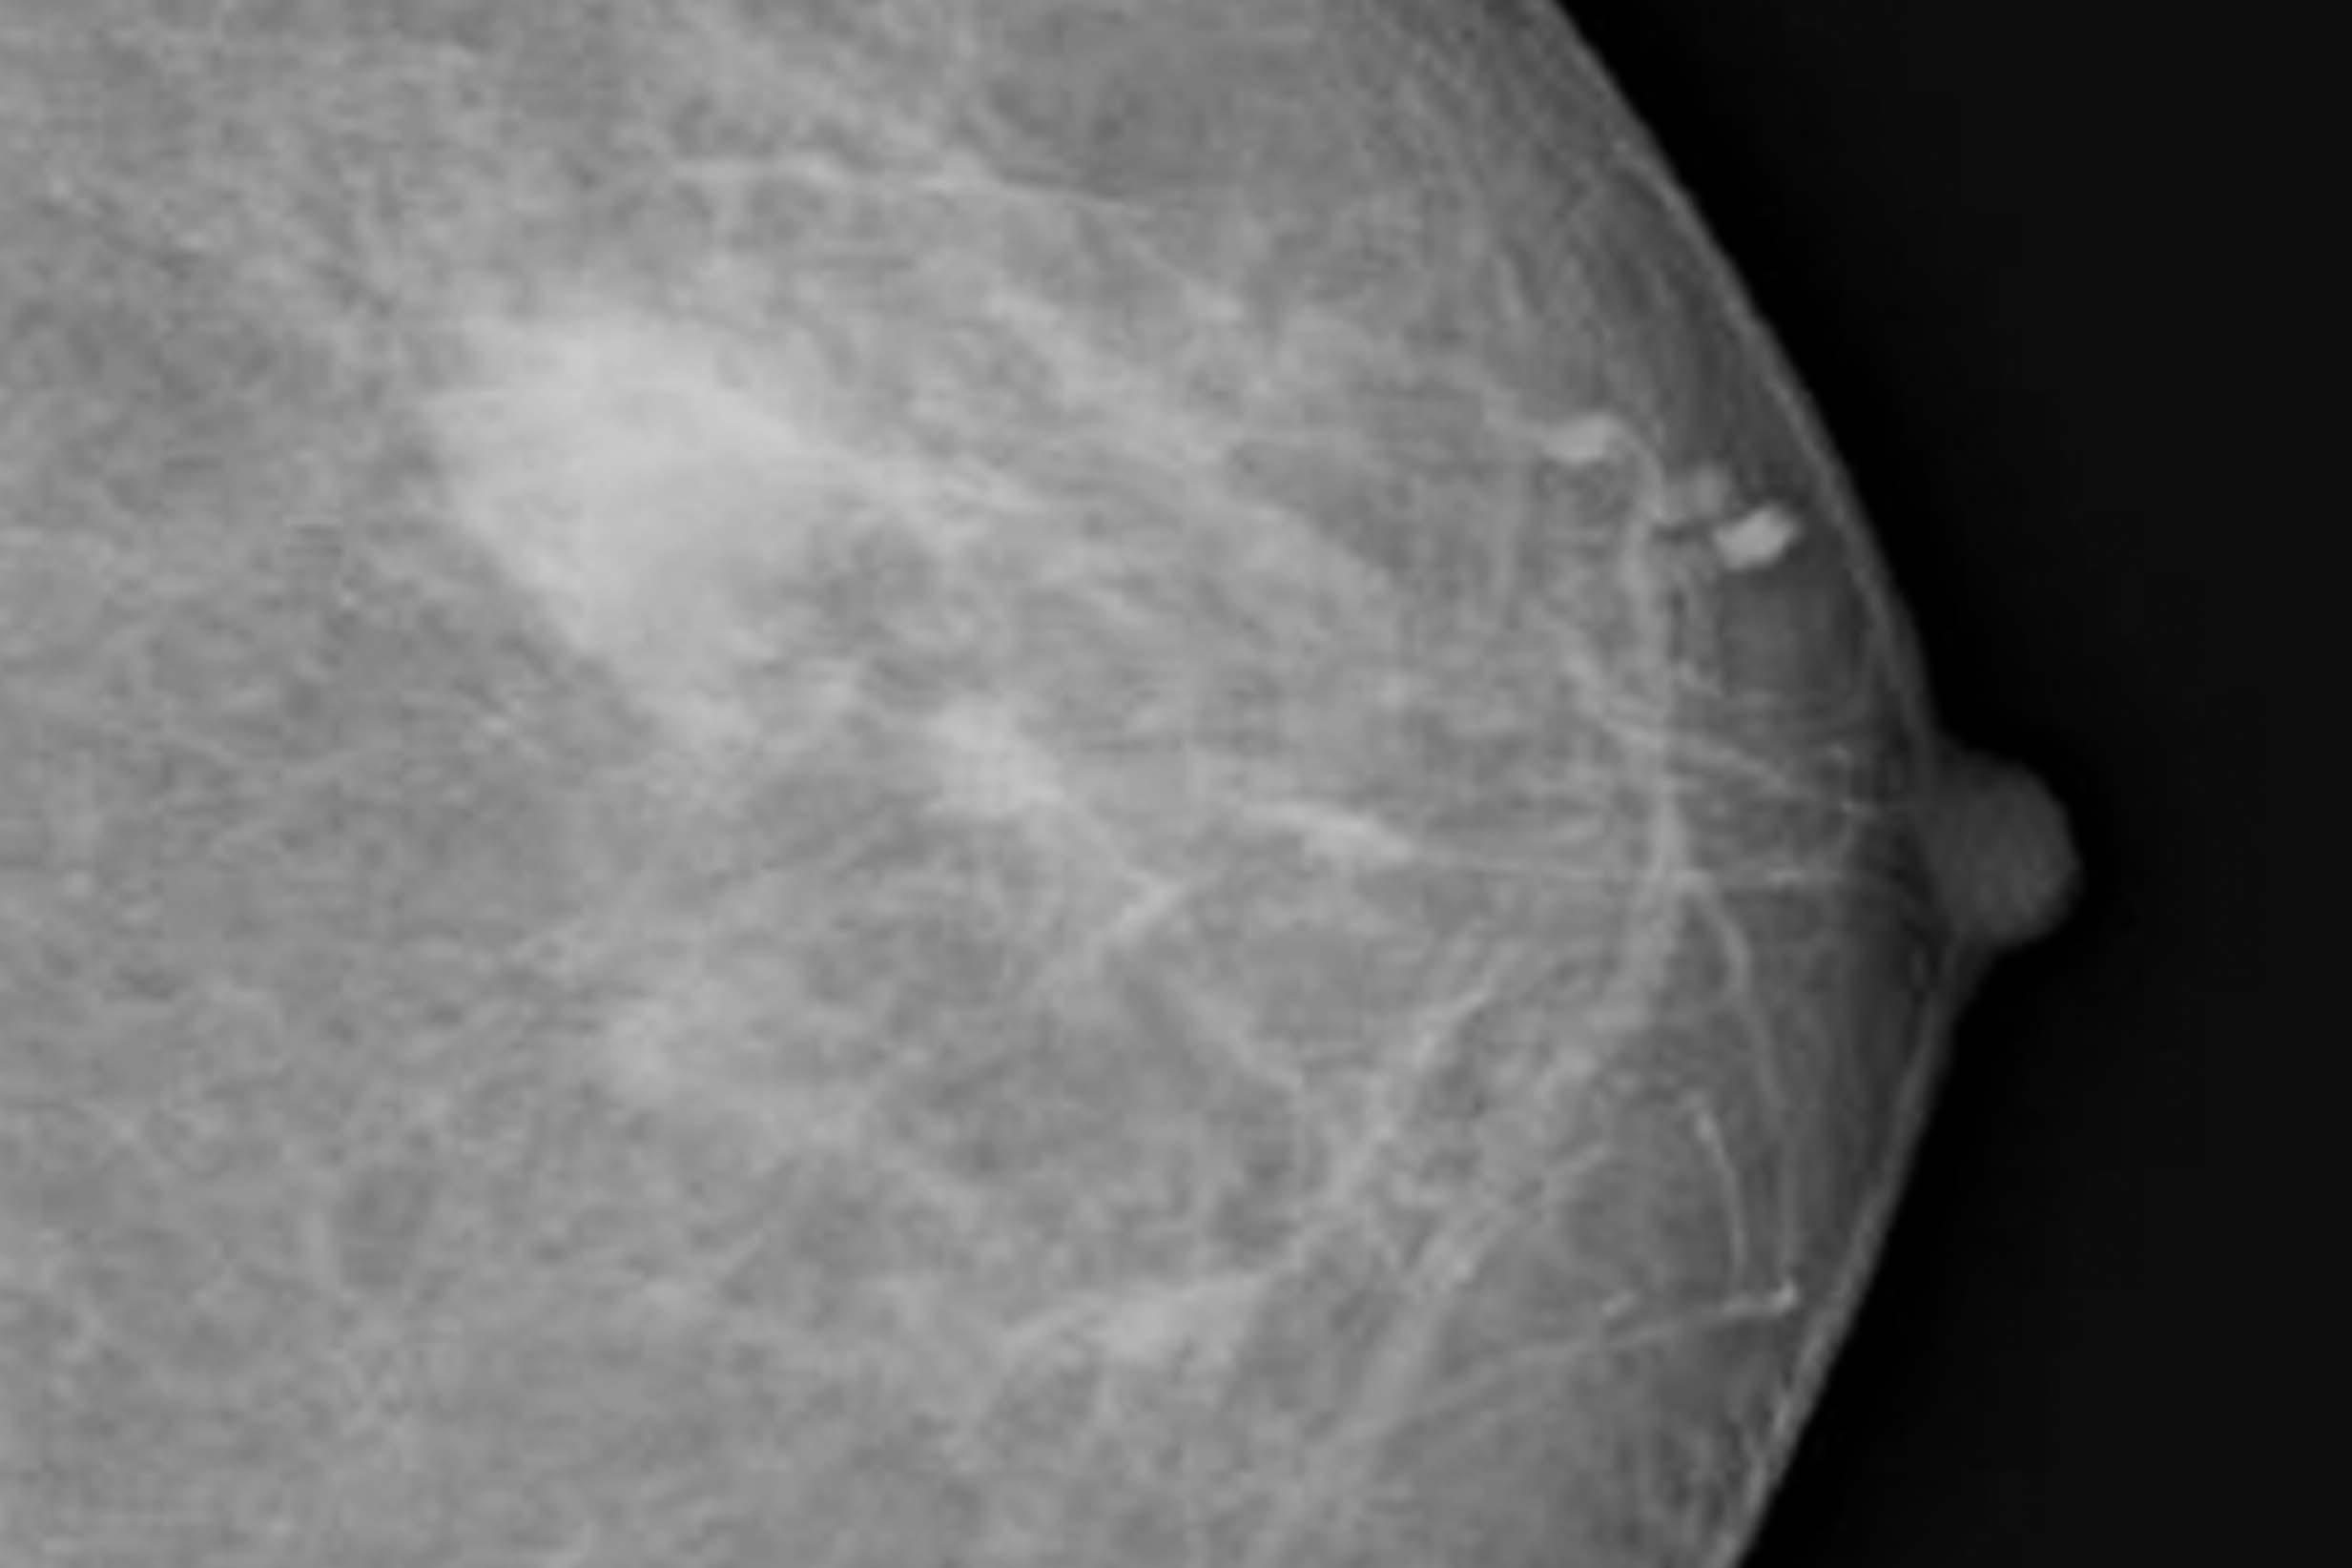

How cysts look on a mammogram

Most cysts show up on mammograms. On a mammogram image, a cyst may look like a smooth round or oval mass with distinct edges. A cancerous tumor is more likely to look like it has an irregular shape and less defined borders.

But mammograms alone usually can’t be used to diagnose a cyst. One of the reasons for this is that mammograms can’t definitively show if a mass is solid or filled with fluid.